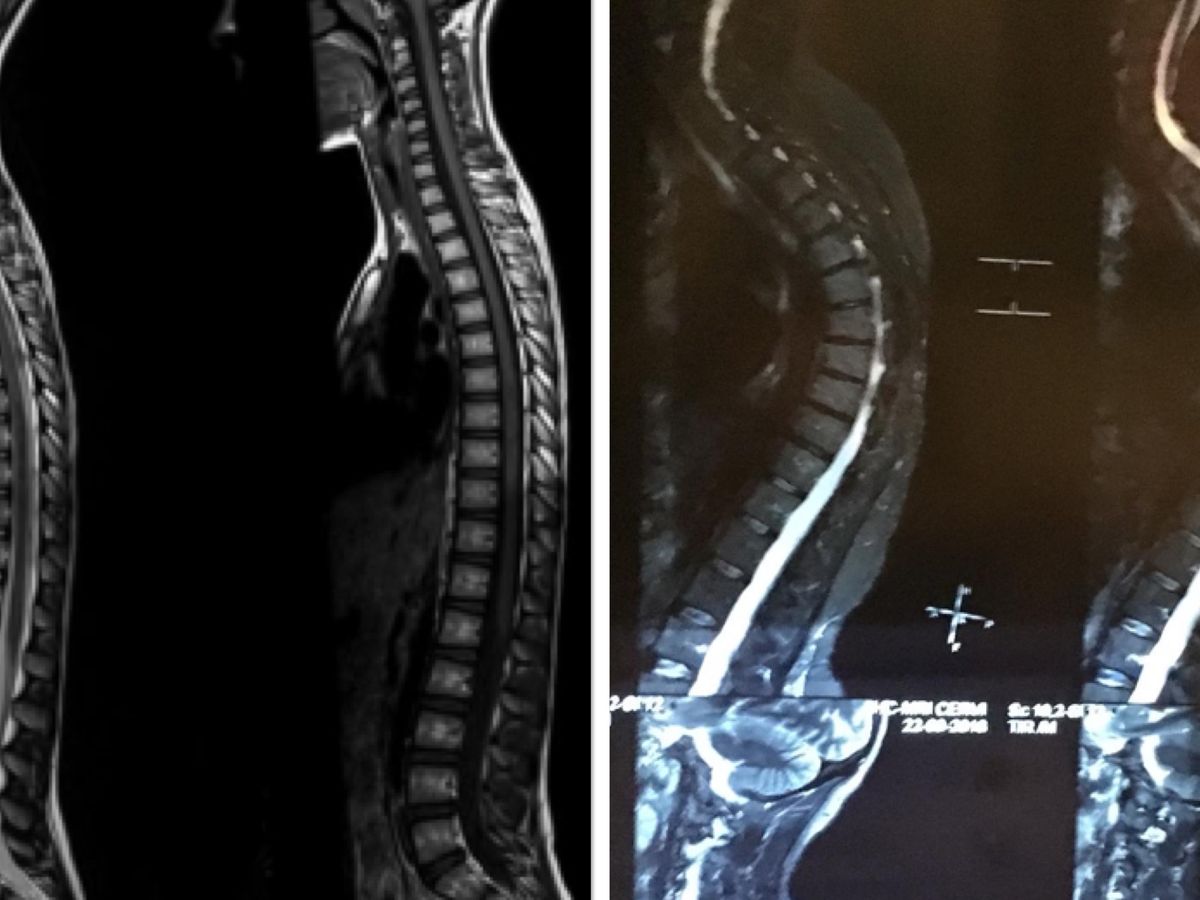

I found out my disability claim was rejected again. I had already supplied a huge amount of evidence to them but somehow I got the exact same score I did in 2018 - 10 out 20 points. You need 20 points to allegedly be accepted. They gave me 10 points again for my spine but have given me 0 for mental health despite having four reports from three different psychologists stating the severity of my issues. I was told I had 13 weeks to get more “evidence”.